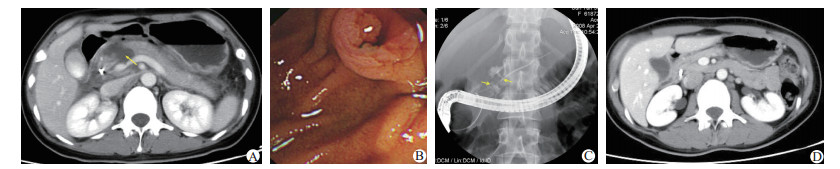

2.2 辅助检查13例患者均行血清淀粉酶检测,血清淀粉酶升高8例。外伤24 h内入院的10例患者中,7例血清淀粉酶检测升高(826±265) U/L;外伤24 h后入院的3例患者中,1例血清淀粉酶检测升高(1 063 U/L)。13例均行术前超声检查,提示胰腺损伤6例,其中疑似胰腺断裂3例。11例行全腹平扫加增强CT,其中7例增强CT静脉期可明显显示胰腺断裂区裂口形状;4例胰腺实质部分裂伤,可见点片状、分枝状出血(图 1A);磁共振胰胆管造影(magnetic resonance cholangiopancreatography, MRCP)明确胰管断裂1例,内镜逆行胰胆管造影(endoscopic retrograde cholangiopancreatography, ERCP)明确胰管断裂3例(图 1B、C)。胰颈部偏门静脉左侧断裂2例,胰体断裂11例。

| 图 1 患者术前术后影像学检查结果及术中所见[A:患者术前CT扫描,箭头处胰头破裂,胰腺形态大,密度混杂;B:内镜逆行胰胆管造影(ERCP)见十二指肠壁充血水肿,乳头有血性液体流出;C:箭头处可见胰腺颈体部主胰管有造影剂外渗;D:ERCP治疗4个月后复查CT胰头处混杂密度消失] |

2.4 并发症及预后13例患者中,1例合并肝破裂患者术后因多脏器功能衰竭死亡,其余12例患者痊愈(图 1D)。术后8例出现并发症,包括胰漏3例、出血1例、感染1例、胰腺假性囊肿3例。3例胰漏患者经通畅引流并冲洗后痊愈;1例出血患者给予生长抑素及对症治疗后出血停止;2例胰腺假性囊肿患者经穿刺置管引流痊愈,1例自行吸收。随访本组胰体尾切除患者,1例出现继发性糖尿病。